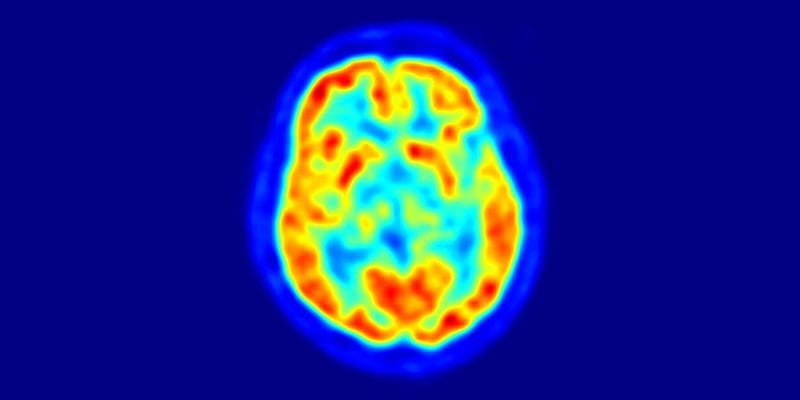

Nuclear medicine procedures administer tiny amounts of radiopharmaceuticals to a patient to obtain functional information about organs, tissues and bone. A special camera is used to detect gamma rays emitted by the radiopharmaceuticals and create an image of the body part under study. The information is recorded on a computer screen or on film.

This is a transaxial slice of the brain of a 56 year old patient (male) taken with positron emission tomography (PET) / Image © Jens Maus, Public Domain

Nuclear medicine imaging

Image © Jens Maus, Public Domain